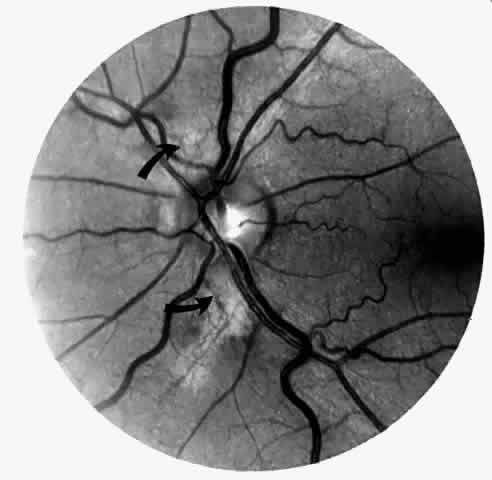

Disc Sign

Transient dark red spots (similar to conjunctival commas), representing plugs of sickled erythrocytes within superficial capillaries, may be seen on the surface of the optic disc (Fig. 3 and Color Plate 1A). These disc changes are not associated with any functional or anatomic abnormalities. They are found in 11% of all patients with sickle cell disease, but appear to be more common in patients with homozygous sickle cell anemia, occurring in 29% of these patients.67 The disc sign correlates with the presence of conjunctival commas and ISCs.

Fig. 3. Disc sign showing dilated loops (arrow) and multiple comma-shaped vascular segments.